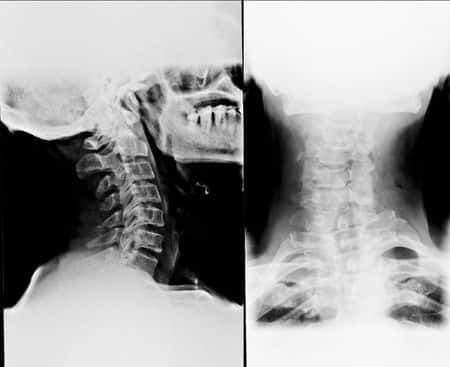

I reviewed the electromyography (EMG) and nerve conduction study. It was abnormal, consistent with cervical radiculopathy involving right C5-C6, bilateral C6-C7, and bilateral C8-T1 nerve roots. The abnormalities on the EMG were consistent with the motor vehicle accident. The MRI of the cervical spine showed disc herniations without adjacent osteophytes at the C3-C4 through C5-C6 levels and at the C7-T1 level. These findings were consistent with the motor vehicle accident.

• Cervical disc herniations C3-C4 through C5-C6 and C7-T1